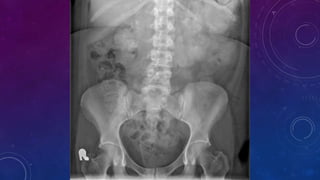

MULTIPLE GALL STONES

GB AND RIGHT RENAL CALCULI.

CHRONIC CALCIFIC PANCREATITIS